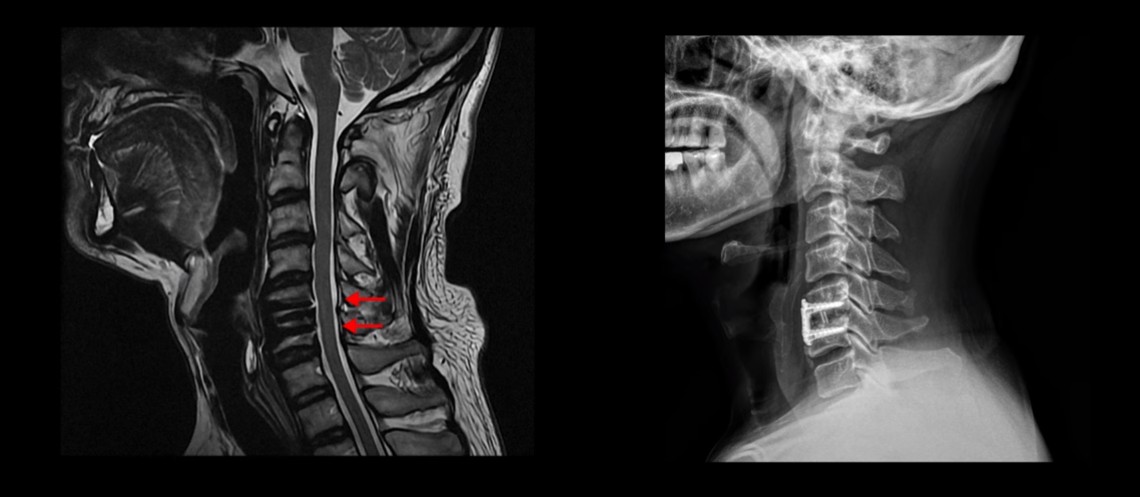

MRI를 보시면 목 5번 6번 마디에 나사가 박힌 유합술이 되어있습니다.

제자리에 나사가 잘 박혀 있고 유합술은 크게 문제가 없는 것으로 보입니다.

이 환자분의 증상인 목, 어깨, 등 통증, 두통, 어지럼증, 눈 불편함, 시력 저하 이런 증상들은 원래가 목 근육 문제와 매우 밀접하게 관련된 증상들입니다. 저희가 목디스크, 목협착 환자의 99%는 거북목 환자라고 말씀드렸습니다. 이런 증상들은 거북목과 매우 밀접한 관련이 있습니다.

이분도 X-ray를 보면 완전한 일자목, 거북목 환자입니다.

이런 목의 형태를 가지고 있으면 만성적으로 목과 어깨가 아플 가능성이 높습니다. 앞으로 밀려나간 머리를 목 근육이 붙잡고 있어야 하기 때문에 목, 어깨 근육이 뭉치면서 아프기 쉽습니다. 또 목 근육과 머리 뒤쪽 근육이 연결되어 있으므로 목 근육이 뭉치면 머리 근육도 뭉치면서 두통도 생길 수 있습니다. 또한 거북목은 목 앞쪽 근육이 짧아지면서 심하게 뭉치는데, 이 목 앞쪽 근육 사이로 얼굴 쪽으로 가는 수많은 신경과 혈관이 지나갑니다. 그래서 신경과 혈관이 영향을 많이 받기 때문에 어지럼증, 눈 통증, 눈 침침함, 이명 같은 증상이 생길 수도 있습니다.